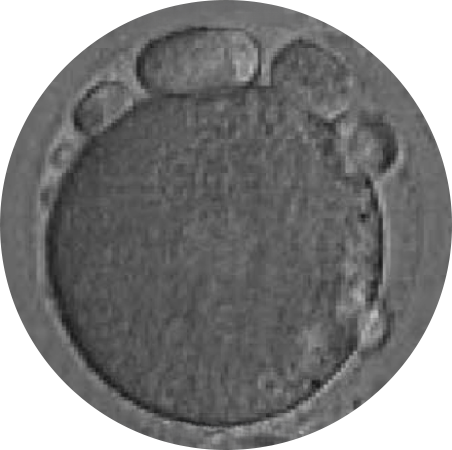

POOR OOCYTE QUALITY

RESTORED EGG

2. Differences Between Restored & Non-Restored Eggs

The eggs provide the acrosomal spindle responsible for dividing the genetic material after fertilization.

Genetic errors that occur during this step are the most important reason why an embryo fails to implant and are the leading cause of early miscarriage.

In women with low-quality eggs (due to advanced age, endometriosis, PCOS, etc.), the cytoskeleton may be disorganized or weakened, which affects the formation of the acrosomal spindle.

If the spindle does not form properly:

- The egg cannot correctly divide its genetic material.

- This can lead to embryos with chromosomal errors, such as trisomies (e.g., Down syndrome).

With IVF MORE®:

- The egg’s metabolism is restored and the cytoskeleton is reorganized.

- This improves the formation of the acrosomal spindle, supporting accurate genetic division.

- The result is a higher number of viable embryos and a lower rate of genetic abnormalities.